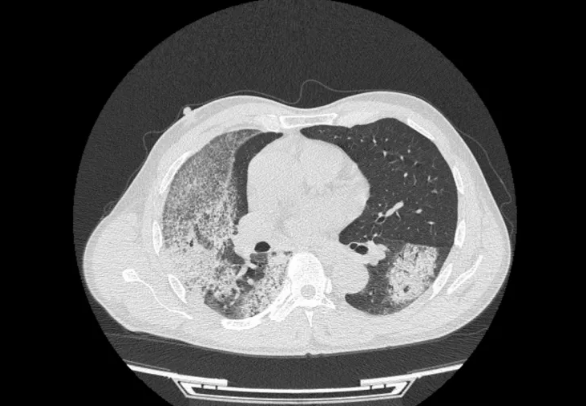

△入院时胸部CT图像

注:图像显示双肺多发渗出病灶,以右肺为著

入院时,王先生血肌酐飙升至699μmol/L,尿检提示大量红细胞,血红蛋白仅81g/L,呈中度贫血,同时,他的抗髓过氧化物酶抗体(MPO-Ab)>400.00 RU/ML,远超正常值。咯血的背后,是致命的肺出血。对于ANCA相关性血管炎患者来说,咯血不仅仅是呼吸道症状,更可能意味着肺部微血管正在被自身免疫系统攻击,导致肺泡出血。若不及时控制,可能迅速发展为弥漫性肺出血,引发呼吸衰竭,甚至窒息死亡。